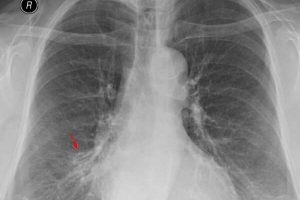

Спайки и другие изменения после пневмонии у взрослых

Плеврально-диафрагмальные спайки — это разросшаяся соединительная ткань между серозными оболочками плевральной полости (ткань, покрывающая стенки грудной клетки и легких). Образования в легких могут быть единичными или множественными. Часто остаточные изменения являются результатом перенесенной пневмонии. В медицине у них есть другие названия — синехии, легочные заболевания или спайки. Общее количество швартов иногда даже приводит к полному …